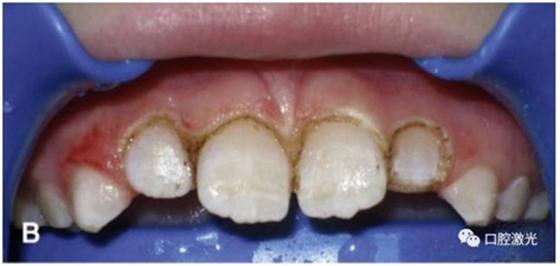

正常情況下,理想的托槽粘接位置為牙冠的中心位置。如果要達到這一目的,正畸牙醫(yī)首先需要能夠從視覺上觀察清楚牙冠的整體形態(tài)。如果存在牙齦覆蓋、遮擋的情況,就很難達到這一目的。這時,簡單的激光牙齦切割就可以很好的增加牙冠的暴露程度,達到更加準(zhǔn)確的粘接托槽的目的,從而也就加快了整個正畸療程的速度。通過下圖的病例可以看到,不僅患者節(jié)約了數(shù)月的等待時間,同時也創(chuàng)造了一個干凈的口腔環(huán)境,降低了在后續(xù)的正畸治療中可能導(dǎo)致牙齦增生的風(fēng)險。

治療前

激光牙齦切割后暴露更多的上前牙便于粘接托槽

當(dāng)天粘接托槽后即刻

4周后即可見明顯效果